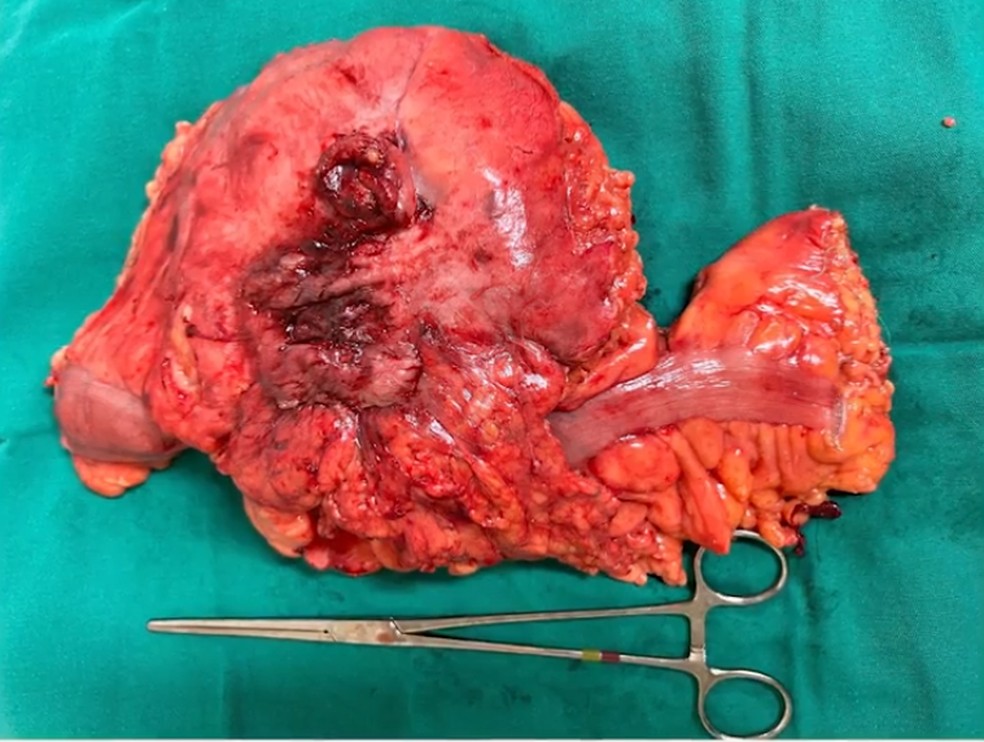

A formação encontrada tinha 13 x 12 x 10 cm, maior até mesmo do que o máximo esperado para um caso de divertículo gigante. Os médicos realizaram, então, uma laparotomia – procedimento de abertura cirúrgica da cavidade abdominal – e confirmaram a existência da massa inflamatória na parede da porção final do intestino grosso.

Em seguida, o tratamento consistiu na ressecção do divertículo junto com uma colectomia segmentar (remoção de parte do intestino grosso) e uma anastomose primária, técnica que restabelece a continuidade do intestino na parte removida. A recuperação pós-operatória foi tranquila, e o paciente recebeu alta no quarto dia.